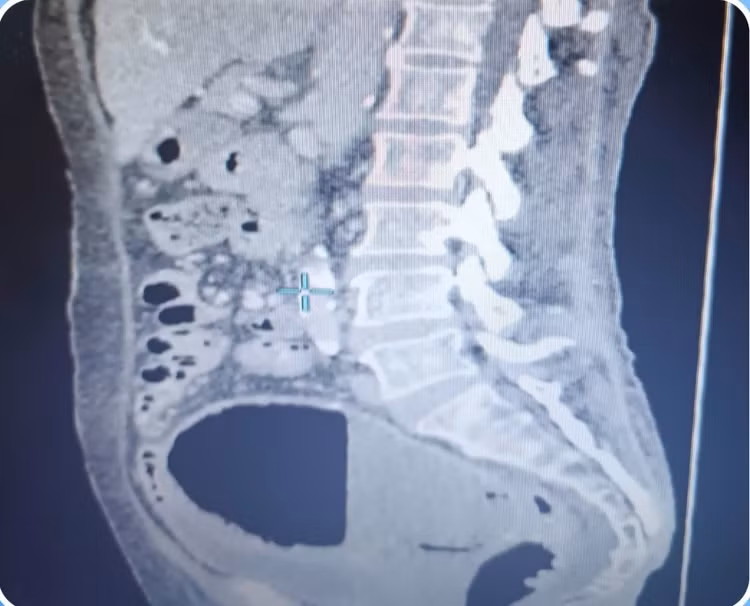

Khi đến thăm khám tại Khoa Sản Phụ Khoa Bệnh viện Đa khoa Xuyên Á, bệnh nhân trong tình trạng đau bụng vùng hạ vị, phần phụ phải ấn đau. Sau khi được chỉ định thực hiện xét nghiệm và chụp MSCT, các bác sĩ chẩn đoán bệnh nhân bị áp xe tử cung và nhiễm khuẩn đường tiết niệu. Đặc biệt, ổ áp xe đã chiếm hết lòng tử cung, có nguy cơ vỡ cao, đe dọa tính mạng.

o-mu-2.jpg

Ổ mủ khổng lồ trên phim chụp - Ảnh BVCC